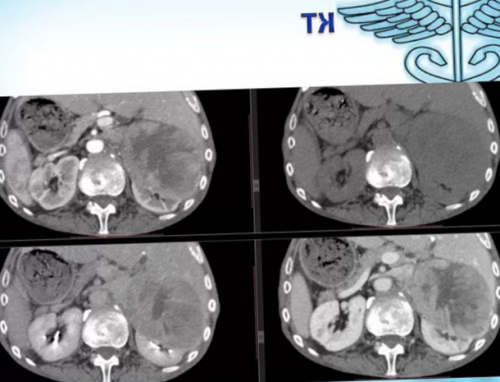

компьютерная томография, позволяющая не только

диагностике осложнения является

диагностики осложнений дивертикулярной

Мультиспиральная компьютерная томография: